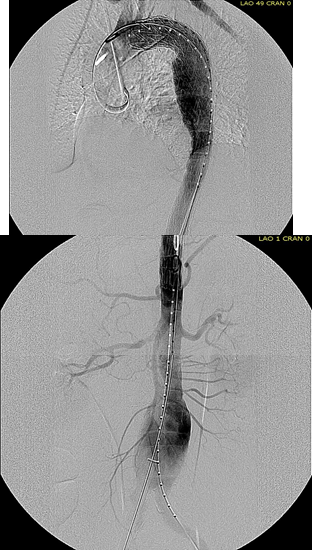

Arteriography from femoral access showed an occlusion of the SMA beyond the middle colic artery, a typical pattern for an embolism that occurs when embolism lodges distally and propogates proximally (image below).

The Penumbra was effective in removing much of the fresh thrombus, but I was also cognizant of the fact that pulling out the catheter will draw clot into the 8F sheath that did not make it into the catheter. I placed a wire, and removed the sheath to expel much of the bulky thrombus (picture below).

The completion angiogram (below) doesn’t show the intermediate angiograms showing thrombus that embolized to other arteries as I manipulated the catheters and thrombectomized -I was able to successfully retrieve these with selective catheterization, another neurointerventional series of maneuvers that I have successfully borrowed.